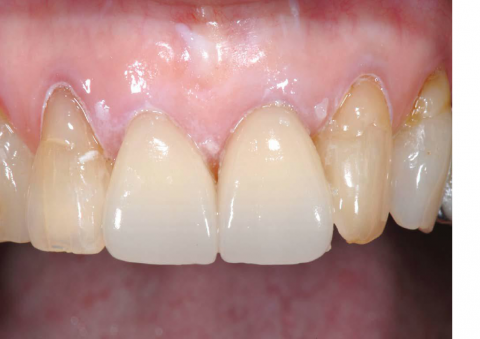

光学印象:審美性、耐久性、アレルギーフリー (2019-04-08)

セラミックには、審美性、耐久性、アレルギーフリーという特徴があります。